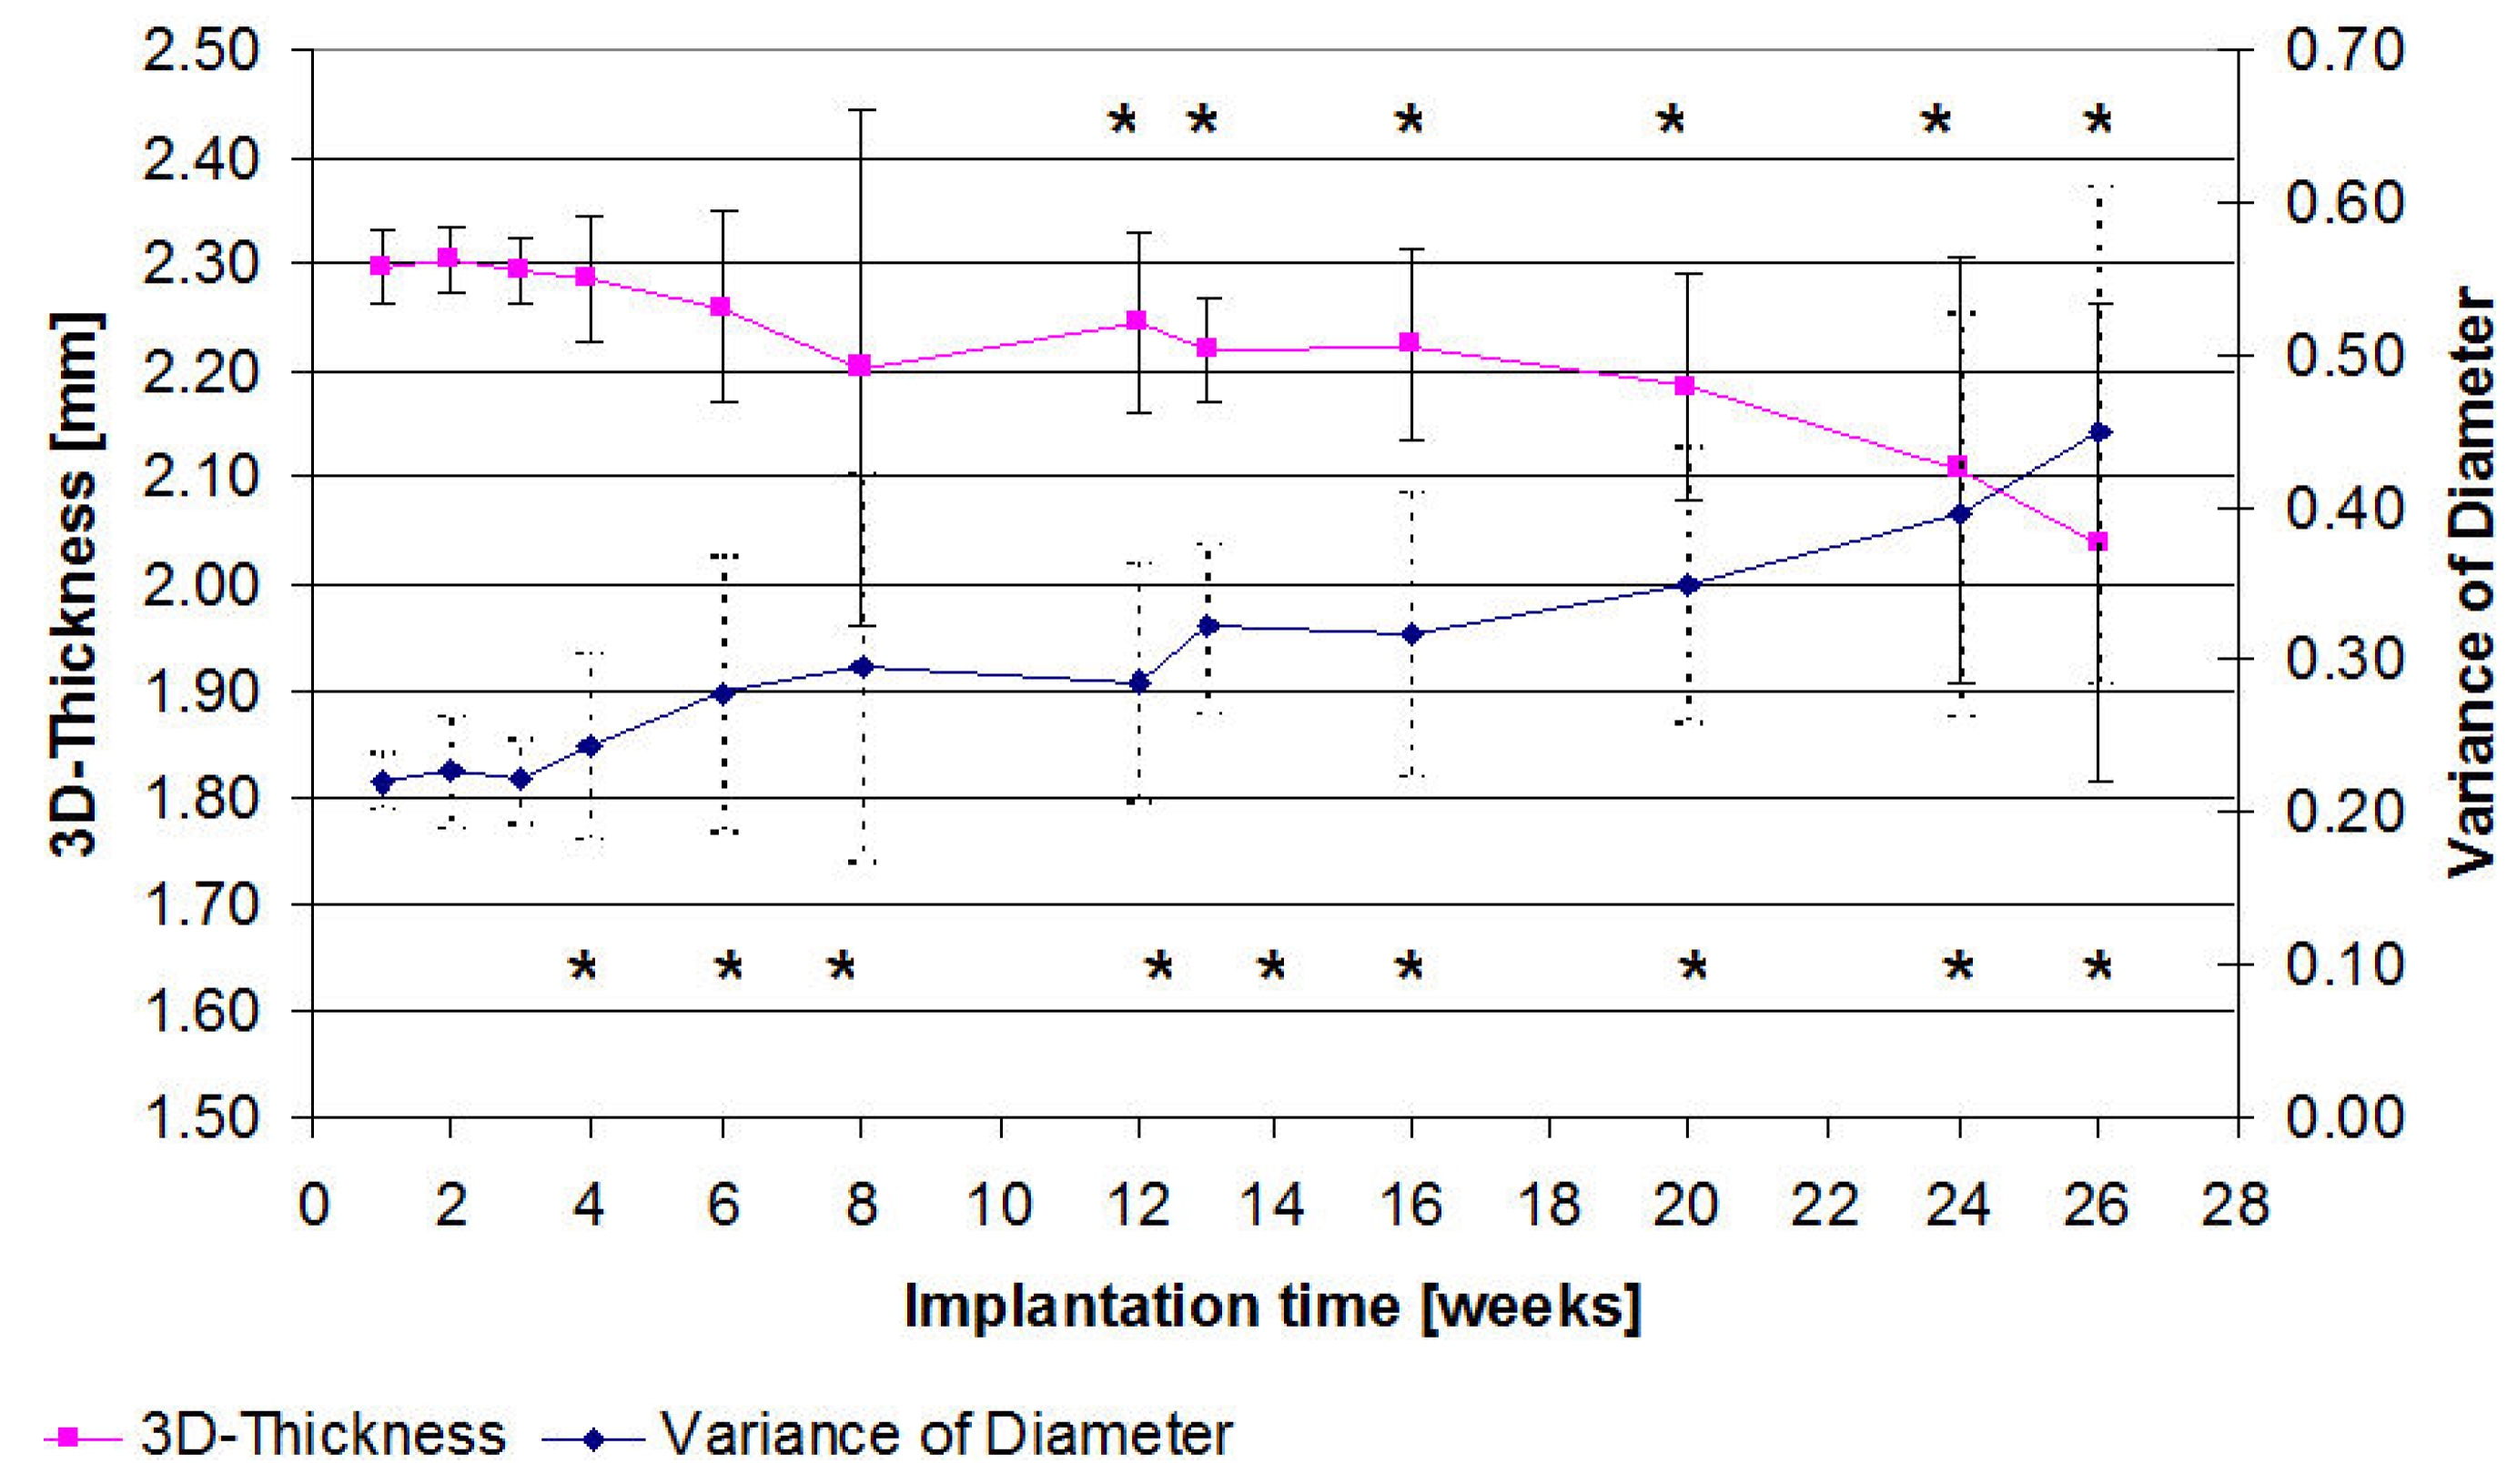

2.3. µ-Computed Tomographic Investigation of the in Vivo LANd442-Pins

3.2.5. In Vivo µ-Computed Tomography